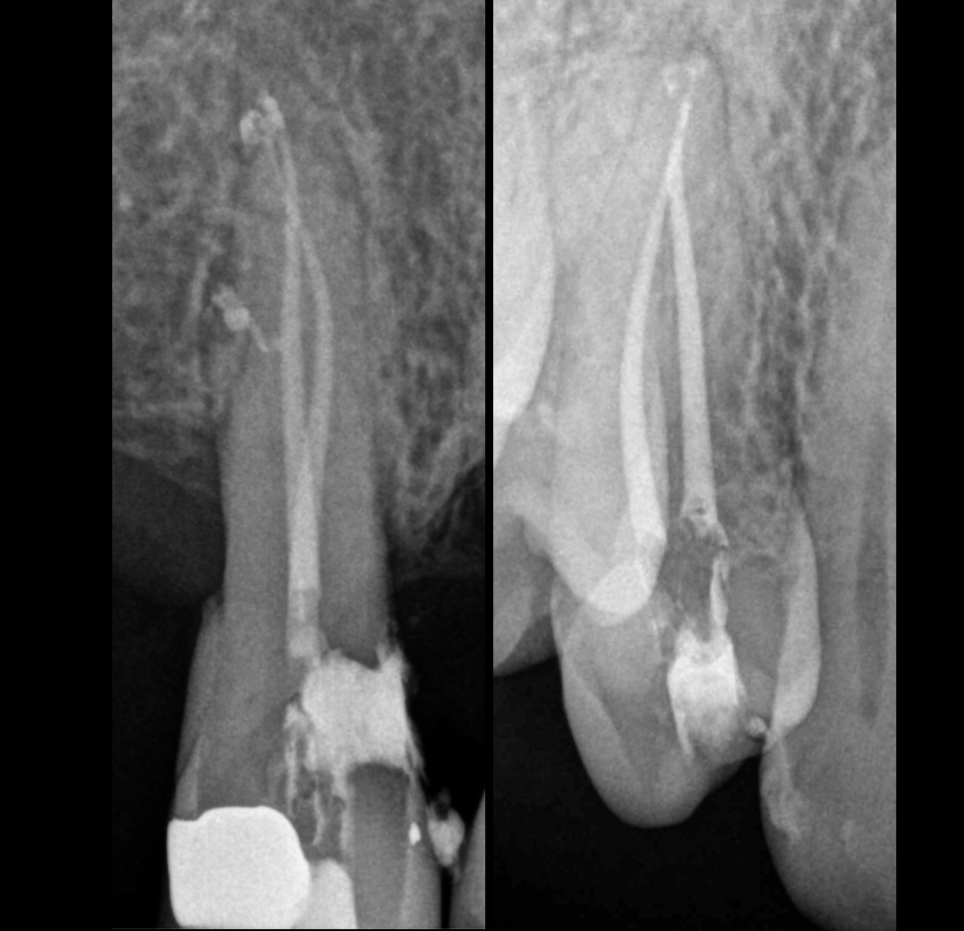

Retratamientos

Gonzaga Zabalegui ofrece la posibilidad de realizar un nuevo tratamiento de conductos en dientes que ya han sido sometidos a endodoncia previa. Este procedimiento se lleva a cabo con el uso de un microscopio, asegurando una visión detallada y un enfoque meticuloso. Su experiencia permite abordar complicaciones y mejorar la salud dental del paciente.